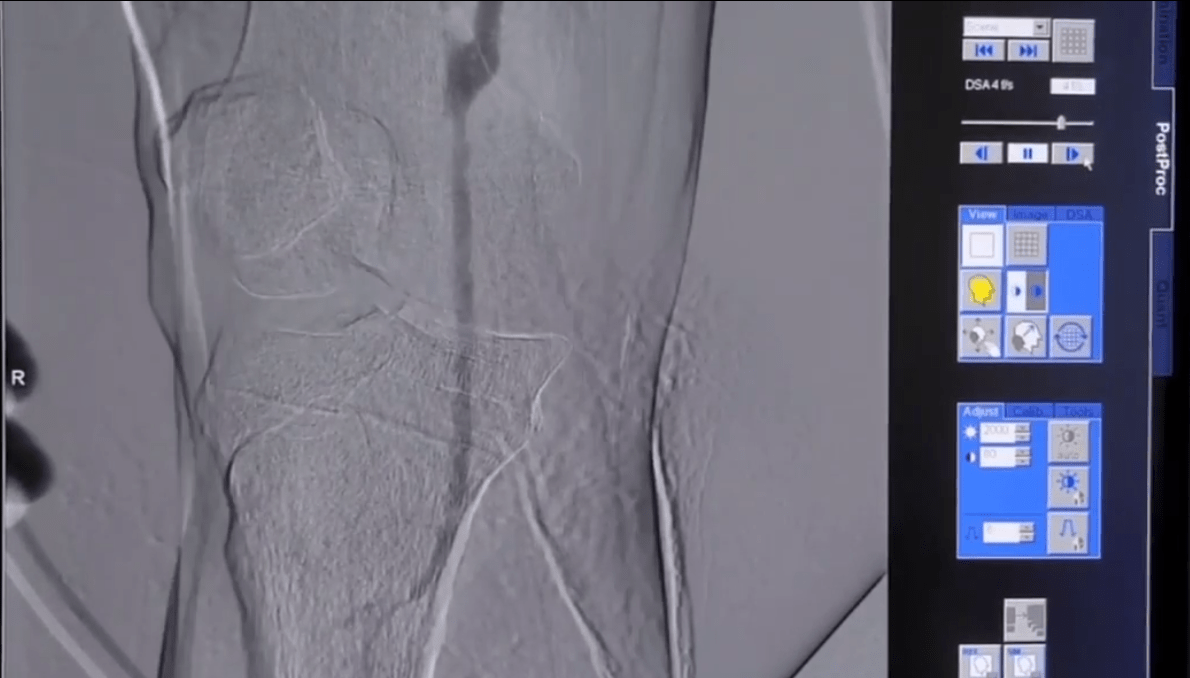

Карбоксіангіографія

Карбоксіангіографія – це метод дослідження артерій нижніх кінцівок, що дозволяє визначити атеросклеротичні ураження (стенози – звуження) в артеріях нижніх кінцівок без впливу на функцію нирок. Кожен фахівець знає, що введення контрастної речовини при ангіографії, наприклад йогексол, йопромід, має ризик ускладнення […]